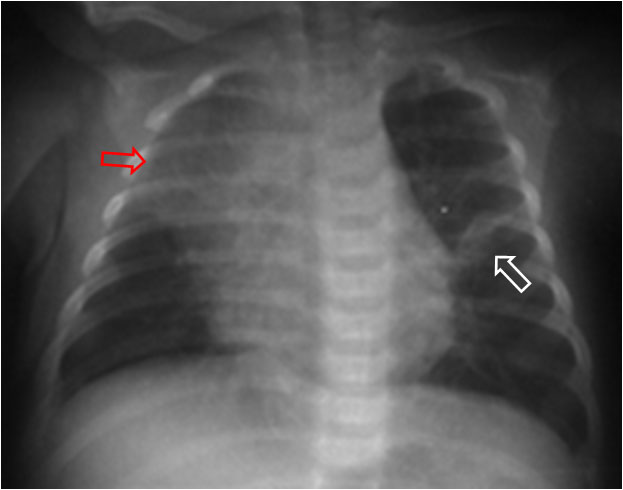

Signo visible en la radiografía de tórax que consiste en una imagen de aumento de densidad de morfología triangular o en «V» que apunta al hilio (flecha blanca). Corresponde a una pequeña atelectasia por tapón de moco y es frecuente verlo en niños con infecciones pulmonares víricas.

En la imagen vemos, además, un colapso del lóbulo superior derecho, de similar causa (flecha roja).